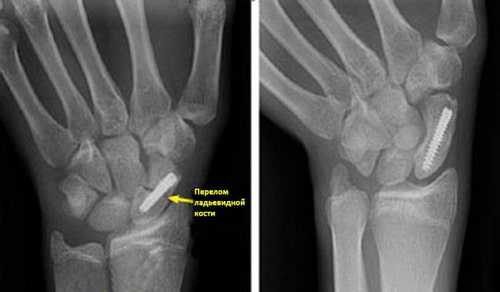

Функция пальцев полная. Сила кулачного схвата правой (доминантной) кисти — 22 кг, снижена почти в 2 раза по сравнению с нормой. Сила схвата левой кисти — 40 кг. Оценка по шкале ВАШ — 3 балла, по опроснику DASH — 21,16 балла. На рентгенограмме (рис. 5, а, б, в) и при компьютерной томографии выявлен ложный сустав ладьевидной кости (см. рис. 6, г). Рис. 6. Пациент К., 19 лет. Диагноз: ложный сустав ладьевидной кости правой кисти. а — рентгенограмма в прямой проекции; б — рентгенограмма в ¾; в — рентгенограмма в боковой проекции; г — компьютерная томография.

(Слева) На рентгенограмме представлен перелом ладьевидной кости, фиксированный винтом. (Справа) Эта рентгенограмма сделана через 4 месяца после операции. Перелом полностью консолидировался.